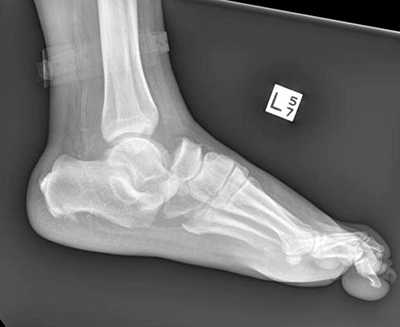

Рентгенологическое исследование

Для диагностики повреждения сустава Шопара делают рентген, КТ и МРТ. На передне-задней рентгенограмме определяют величину пяточно-кубовидного угла. Проводят одну касательную к наружному краю кубовидной кости и вторую касательную к наружному краю пяточной кости. В норме угол между касательными колеблется в пределах от 0 до 5°. Увеличение угла свидетельствует о нарушении стабильности пяточно-кубовидного сочленения. КТ во фронтальной и сагиттальной плоскостях позволяет выявить дефект суставных фасеток, смещение костей при вывихе и фрагментацию костей при переломе. КТ, по сравнению с рентгенографией, является более информативным методом диагностики. МРТ позволяет выявить дефекты отдельных связок.

Рис. 8. Переломо-вывих в суставе Шопара

Рис. 9. Переломо-вывих в суставе Шопара